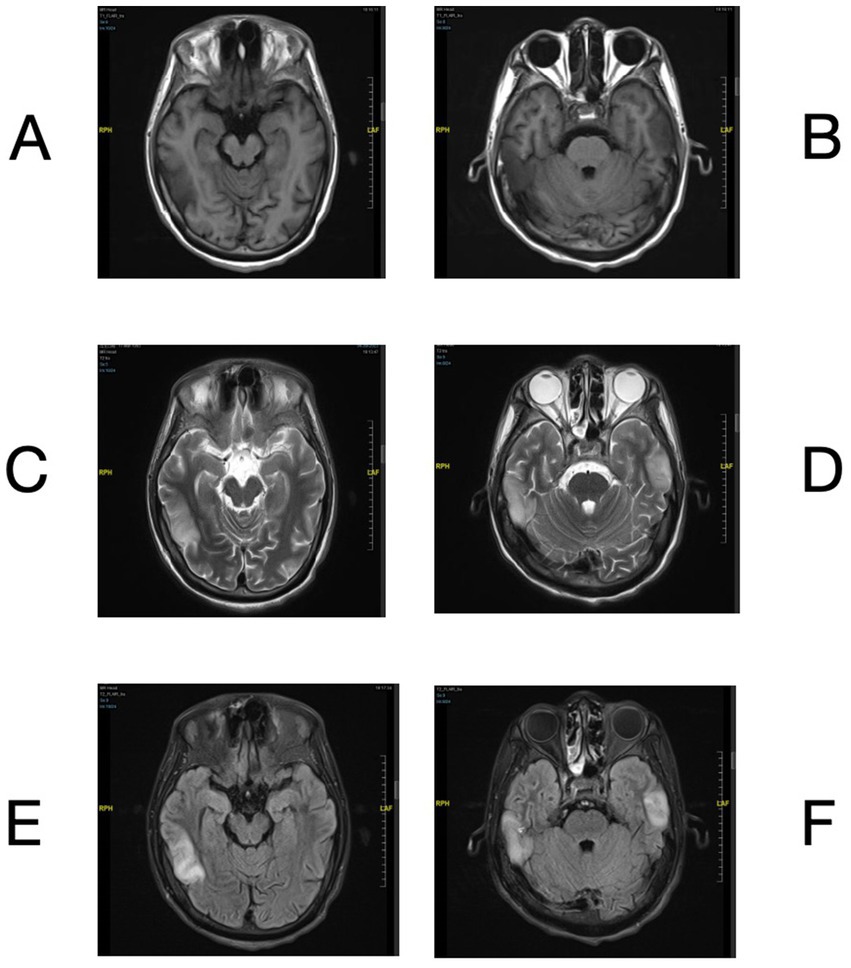

A 30-year-old man presented to the emergency room on August 1st, 2023, with a sudden onset of dyslexia, logasthenia, and an expressive language disorder that began 3 days prior to admission. He did not report any headache, dizziness, hallucinations, limb numbness, or psychiatric disorders. Cranial magnetic resonance imaging (MRI) revealed multiple abnormal signals in the bitemporal lobes (Figures 1AF). His vital signs were generally normal, except for a fever of 38°C. Physical examination showed negative meningeal irritation signs but indicated severe vision impairment, with a visual acuity of 0.1 in the left eye and only light perception in the right eye. A lumbar puncture performed the next day revealed an increased white blood cell count with a predominance of monocytes, as well as slightly elevated protein levels in the cerebrospinal fluid (CSF). Significantly elevated levels of interleukin (IL)-6, IL-8, and IL-10 were also noted (Supplementary Table S1). Tests for traditional bacteria and fungi culture and autoimmune encephalitis-related antibodies in the CSF were negative. Additional tests screening for cytomegalovirus (CMV) DNA, Epstein–Barr virus (EBV) DNA, polyomaviruses BK and JC DNA in the CSF, antibodies of CMV, EBV, rubella virus, parvovirus B19 and herpes simplex virus in the blood all yielded negative results. To elucidate the etiology of the patient’s condition, CSF and blood samples were collected and subjected to mNGS for pathogen screening. Whole exome sequencing previously revealed a novel but deleterious mutation, c.1880A > G (p.Tyr627Cys), in exon 17 of the BTK gene on the X chromosome, which was confirmed to have been inherited from his mother, a heterozygote. This finding supported his diagnosis of X-linked agammaglobulinemia (XLA).

Figure 1

www.frontiersin.org

Figure 1. Brain MRI of bilateral temporal lobe lesions. Brain MRI showed T1 hypointensity (A,B) and T2 hyperintensity (C,D) in bilateral temporal lobes. The lesions exhibited hyperintensity on the FLAIR sequence (E,F).